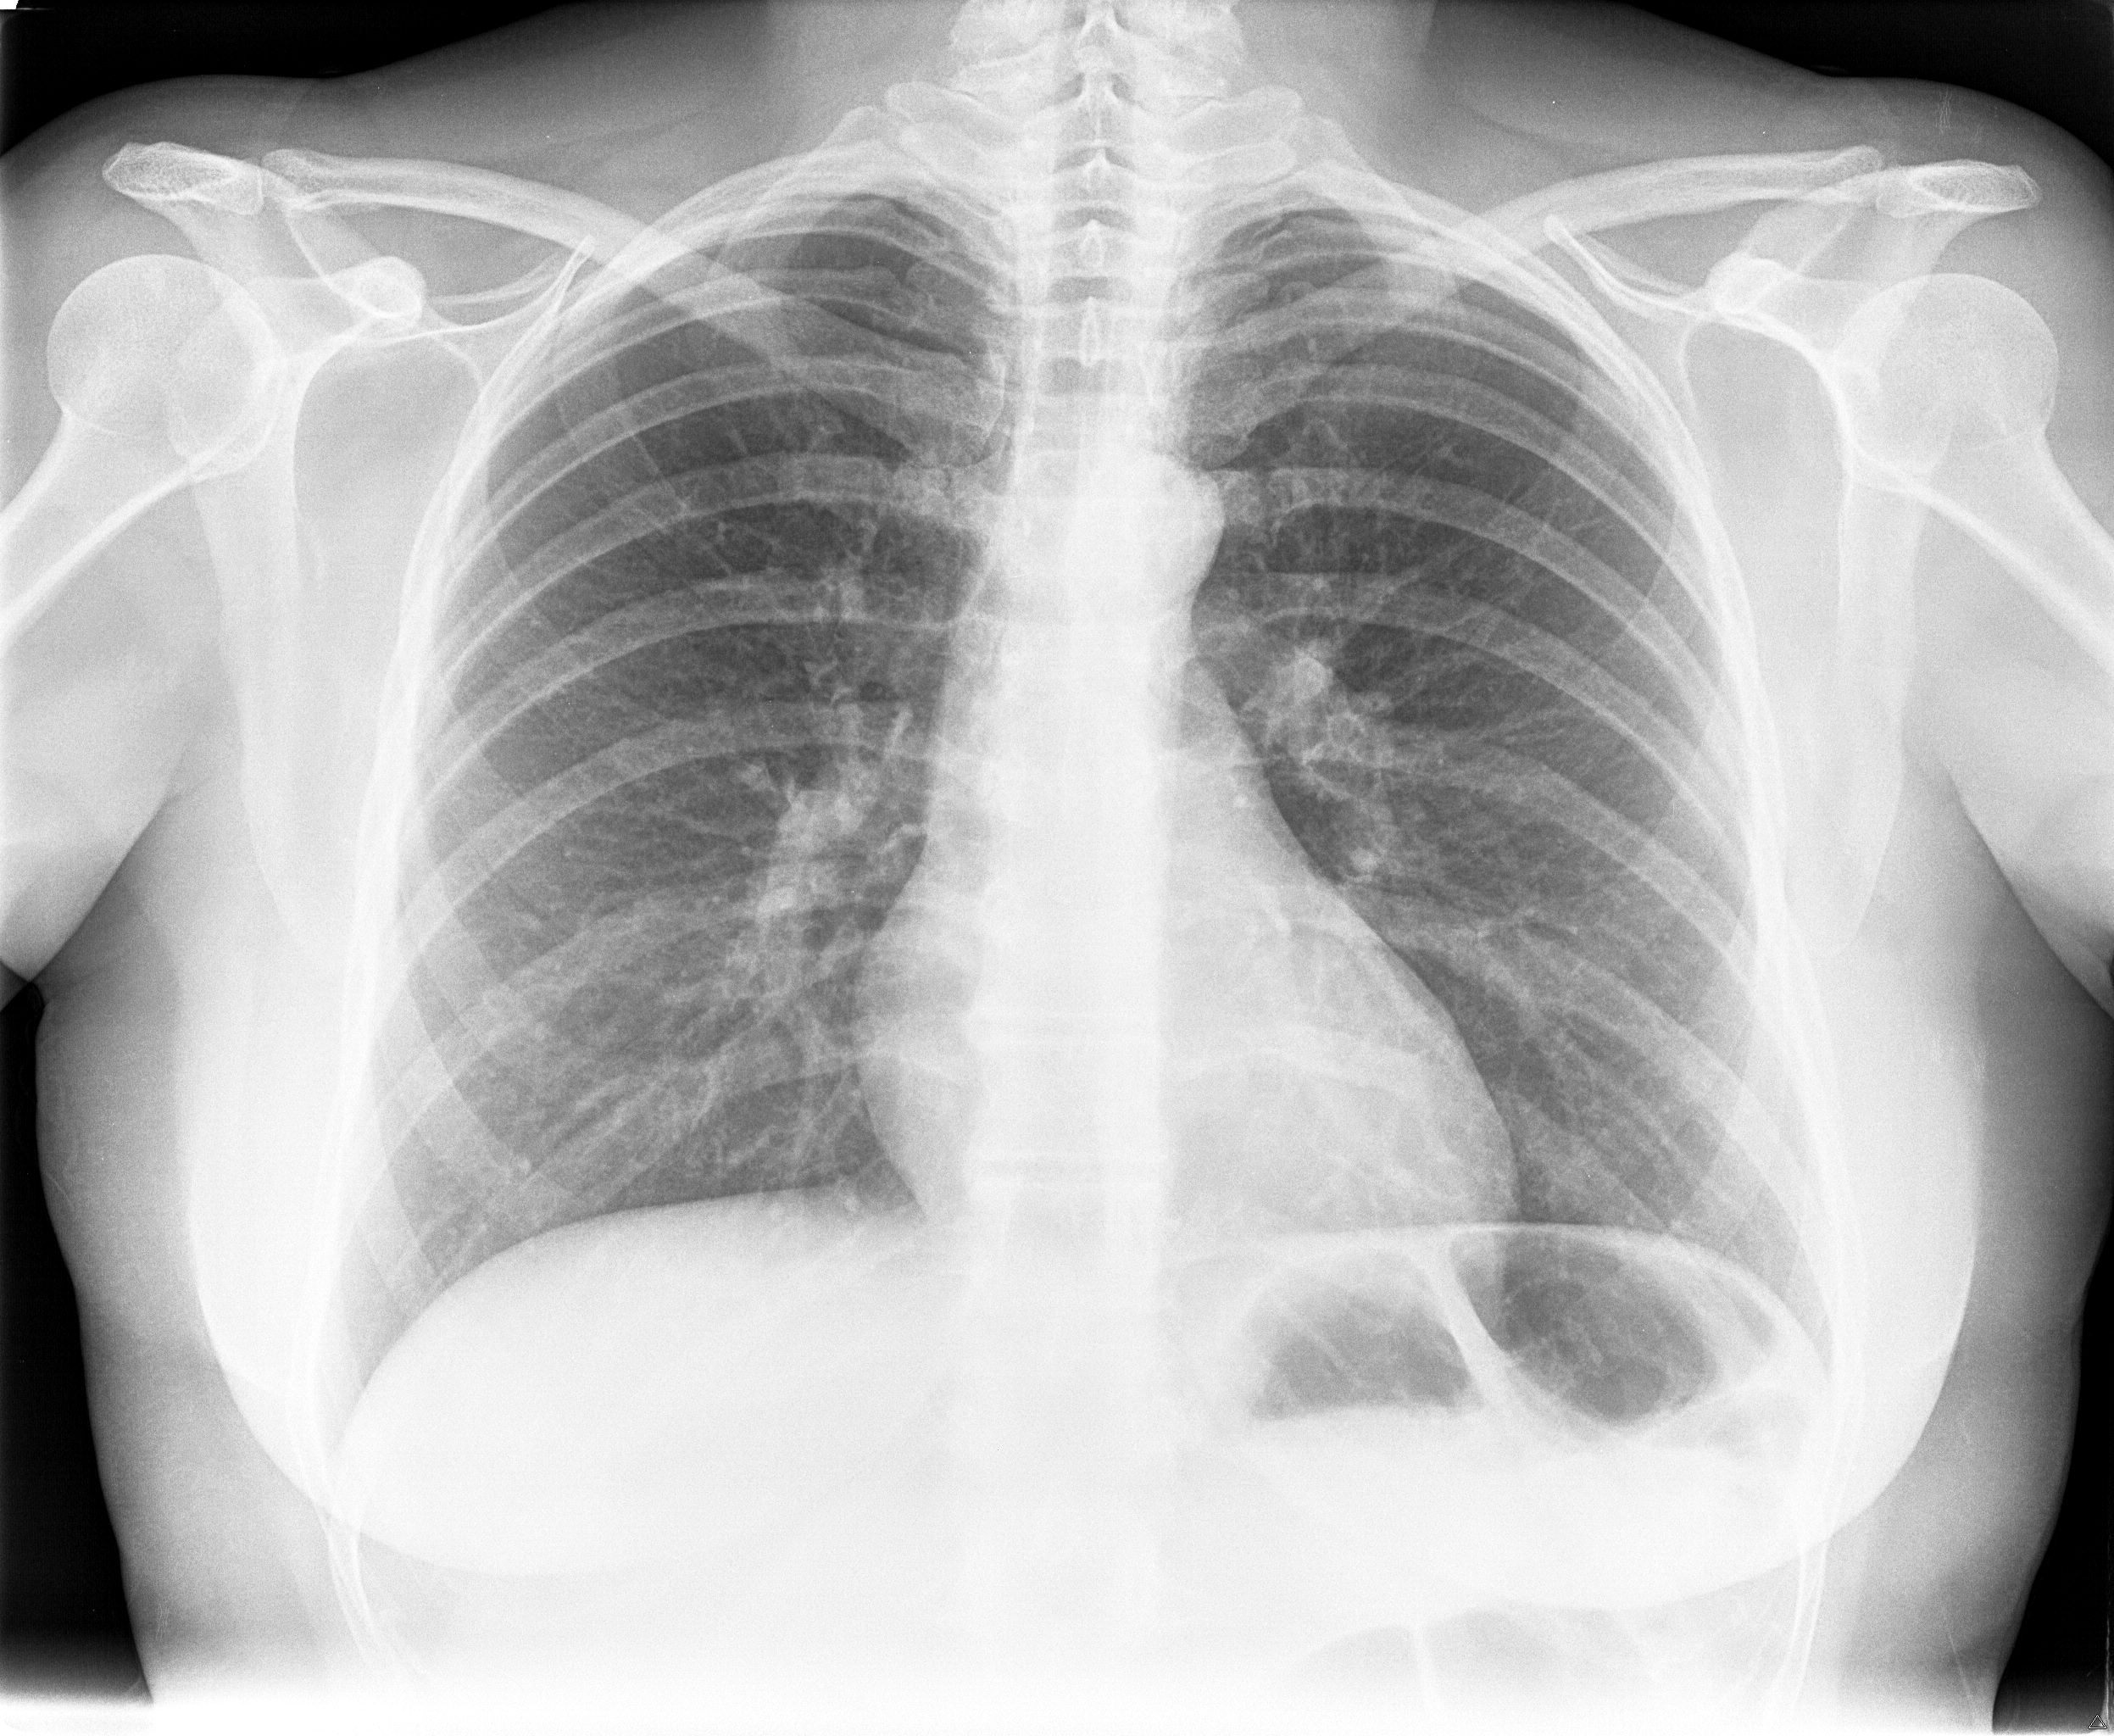

buongiorno dopo tutta una serie di esami effettuati nel corso di quest anno (ecocuore, gastroscopia, ecografia addome... tutti negativi) per capire l origine di questo mio fastidio ieri ho fatto i raggi al torace premetto che sono una fumatrice da 10 sigarette al di con un passato da fumo passivo non indifferente...vorrei capire se effettivamente ho qualcosa per cui preoccuparmi specifico che ho 39 anni

ter.jpg

[ 827.99 KiB | Osservato 4171 volte ]